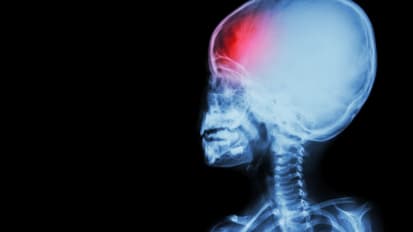

Our team cares for children with common and rare conditions affecting all areas of the nervous system. Broad categories include stroke and cerebrovascular disease, brain injuries, brain tumors, birth defects, epilepsy, movement disorders, development and behavior issues, neuromuscular disorders, headache and sleep disorders.